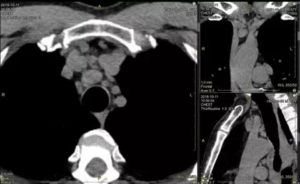

После комплексной диагностики врач определяет причины, которые повлекли увеличение узлов средостения. Лабораторные и инструментальные способы определят движущие силы нарушения. Данная патология исследуется способом компьютерной томографии (КТ), УЗИ (ультразвуковое исследование) грудной клетки, проведением МРТ (магнитно-резонансной томографии).

Больного с положительным результатом на иммунологический тест отправляют на КТ обязательно. Грудная клетка подвергается линейной томографии в исключительных случаях, когда нет альтернативы. Делают флюорографию, рентгеноскопию, выводят на табло прибора трёхмерный снимок.

Сегодня для диагностики средостенной лимфаденопатии применяют компьютерную визуализацию. При этой процедуре специалисты получают самую достоверную информацию. С помощью бронхоскопии медики получают материал для исследования трахеи, бронхов, туберкулёза. Радиография исследует кровообращение и вентиляцию лёгких.